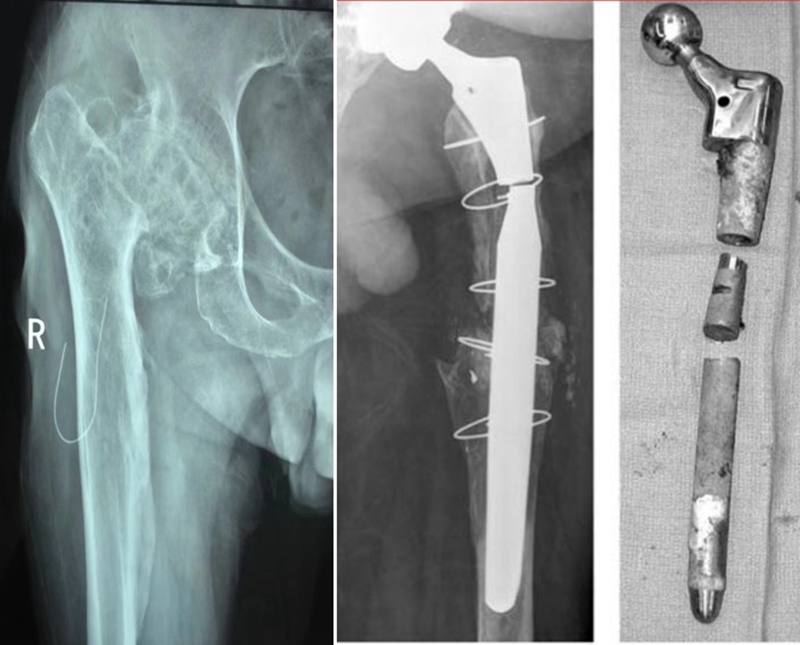

②内固定的取出:良好术野,齐全工具。

③近端的重建:纠正性截骨,短缩截骨。

纠正性截骨的要求是:

①在畸形最严重的部位纠正对线不良;

②最大限度保留骨质;

③截骨部位牢固固定;

④使用长柄假体跨越截骨端。

股骨截骨的不同方法:

股骨近端截骨重建——截骨方式:横形、斜形、阶梯式及双V形截骨

优点:不改变股骨近端的解剖,保持臀中肌附丽点完整,截骨后能矫正股骨的前倾角,是较为理想的股骨缩短方法。

缺点:①骨折——截骨两端捆钢丝;②截骨端不稳定,术后骨折不愈合——足够长的远端固定型非骨水泥型假体或组配型假体,假体长度足够,避免型号过小,必要时使用骨板加强固定;③失血多、时间长。